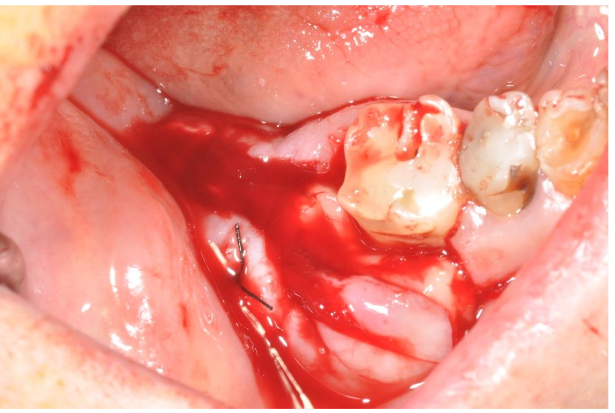

At the end of the cleaning, the cavity was filled by PRGF®-Endoret® autologous membranes to improve the healing processes: indeed, the PRGF improves the formation of new vessels (neoangiogenesis) stimulating the cells migration and differentiation. Immediately after the PRGF application in the cavity an important bleeding appeared due to the opening of the vessels of the surrounding tissues: this is a typical phenomenon of the PRGF application (image 7). It seems that the freedom of nitric oxide from the PRGF is the cause of this bleeding for release of the smooth musculature of the vessels. However, the presence of fibrin clot autologous membranes, another product derived from the PRGF, stopped the bleeding almost immediately (image 8).

The release of platelet’s growth factors promotes several biochemical results: the fibrin clot reduces the risk of bleeding, the increase of the new vessels formation (neoangiogenesis), a chemotactic effect on the cells coming from the surrounding tissues and their transformation in osteoblastic direction (when PRGF is into a bone cavity): indeed, thanks to the degranulation of platelets there is a release of several growth factors (GFs) which are key elements of any healing process. Moreover PRGF®-Endoret® reduces the risk of infections of the wound because the plasma is rich of several molecules of the humoral immunity: antibacterial molecules and immunoglobulins inhibit bacterial growth in the grafted material despite the absence of a protective gingival covering. The real problem was the risk to use an autologous biomaterial rich in growth factors in a part of the body where there probably were some residual cancer cells as the scintigraphic exam showed: anyway, the clinical conditions of the patient, his age and the pain he suffered for several months moved us to take the risk for a surgical approach. To reduce the risk of a bad healing we decided, in accord with the family members, to use pure platelets concentrate (a P-PRP) as PRGF-Endoret. Moreover, we were conscious that there was the risk of a stimulation of the growth of the cancer cells, and for that reason the debridement and the cleaning of the cavity was extremely accurate. To remove the necrotic tissue surrounding the alveolar nerve the cleaning of this part needed a particular attention and precision with lot of difficulties: despite this, there was no problem for the sensibility of this nerve without residual anesthesia or paresthesia.